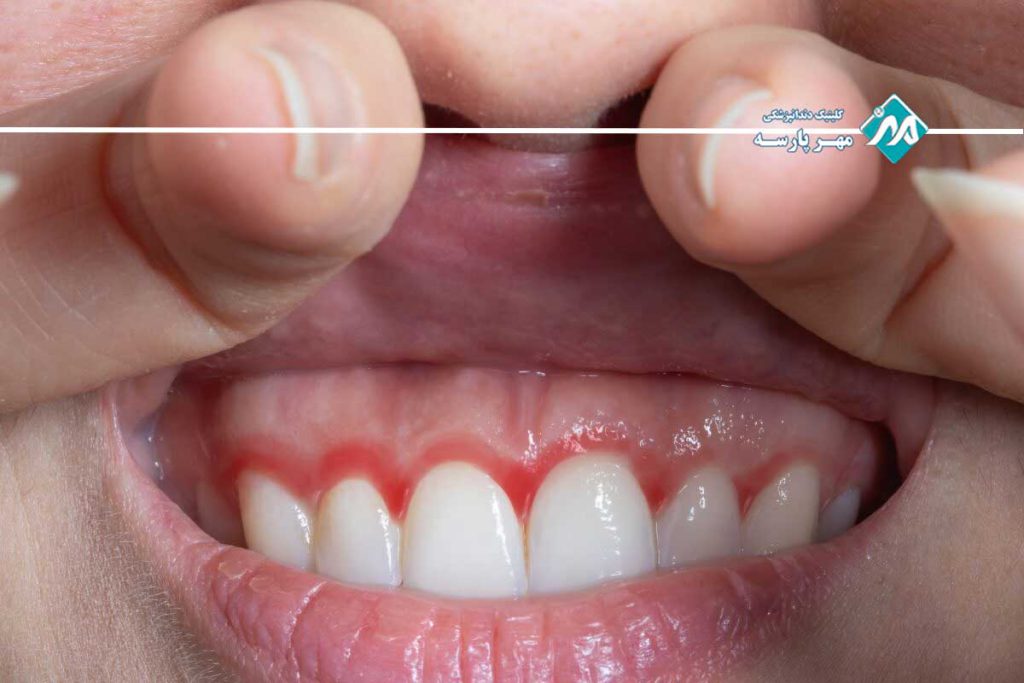

ژنژیویت شایعترین نوع بیماری لثه است که معمولاً به دلیل تجمع پلاکهای میکروبی روی دندانها و لثهها ایجاد میشود. این بیماری باعث التهاب، قرمزی، خونریزی و تورم در لثهها میشود بهویژه هنگام مسواک زدن یا استفاده از نخ دندان. ژنژیویت معمولاً به دلیل رعایت نکردن بهداشت دهان و دندان مانند مسواک نزدن منظم، مصرف زیاد قند و عدم استفاده از نخ دندان ایجاد میشود. خوشبختانه ژنژیویت در صورتی که در مراحل اولیه تشخیص داده شود کاملاً قابل درمان است و با بهبود عادات بهداشت دهان و دندان، التهاب و علائم آن از بین میرود. با این حال اگر این بیماری درمان نشود ممکن است پیشرفت کرده و به انواع شدیدتر بیماریهای لثه تبدیل شود.

- خونریزی لثهها: یکی از شایعترین علائم بیماری لثه خونریزی هنگام مسواک زدن یا استفاده از نخ دندان است. این خونریزی معمولاً نشاندهنده التهاب لثههاست و بهویژه در ژنژیویت مشاهده میشود.

- تورم و قرمزی لثهها: لثههای بیمار معمولاً متورم و قرمز میشوند و این التهاب میتواند باعث حساسیت بیشتر در هنگام لمس یا جویدن غذا شود.